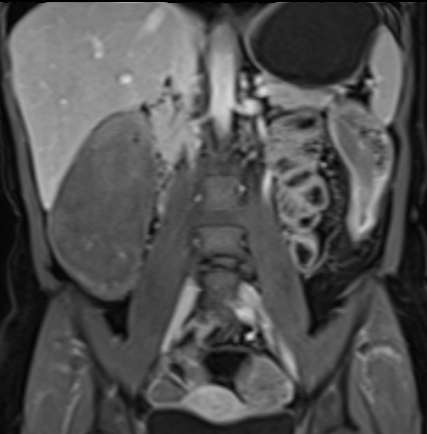

Bệnh nhân nữ 48 tuổi, đang điều trị bằng thuốc kháng TNF, được chỉ định nội soi đại tràng.

Phát hiện hẹp lòng ruột ở đại tràng sigma, không thể vượt qua được khi nội soi.

MR-enterography được thực hiện để đánh giá mức độ lan rộng của chỗ hẹp.

Ruột non bình thường, nhưng ghi nhận các đoạn hẹp ở đại tràng xuống và đại tràng ngang.

Cả hai đoạn hẹp đều có thành ruột dày đến 8 mm và ngấm thuốc rõ rệt theo kiểu niêm mạc ở đại tràng xuống và kiểu phân lớp ở đại tràng ngang.

Giãn ruột trước chỗ hẹp được ghi nhận ở cả hai đoạn.

Do các chỗ hẹp này không hiện diện khi nội soi đại tràng trước khi điều trị kháng TNF, nhiều khả năng chúng đã hình thành trong quá trình điều trị.

Do đó, quyết định phẫu thuật cắt đại tràng gần toàn bộ với miệng nối hồi-sigma đã được đưa ra.